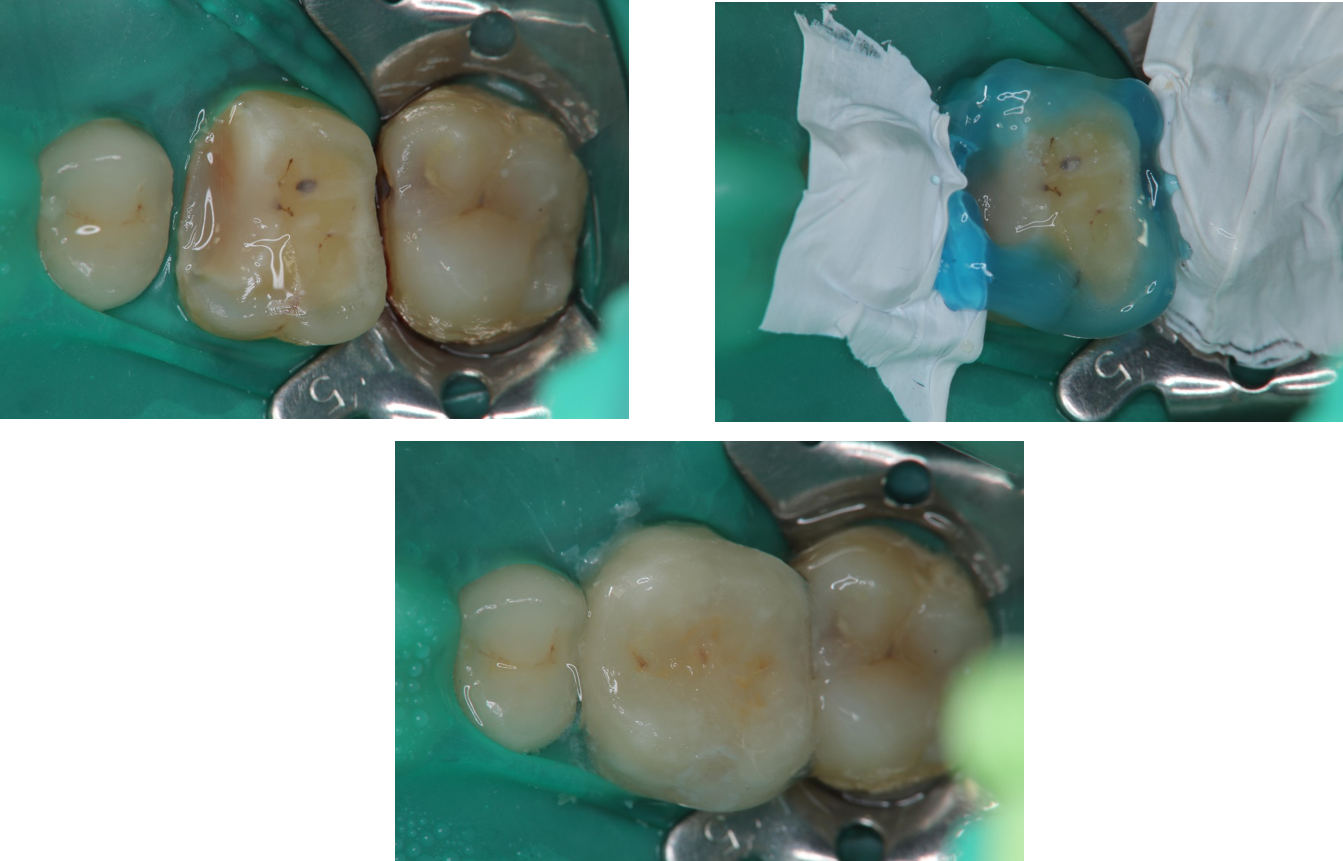

治療前,嚴重二次蛀牙

二次蛀牙

將牙齦下蛀牙移除並預填補

陶瓷冠塊體製備後